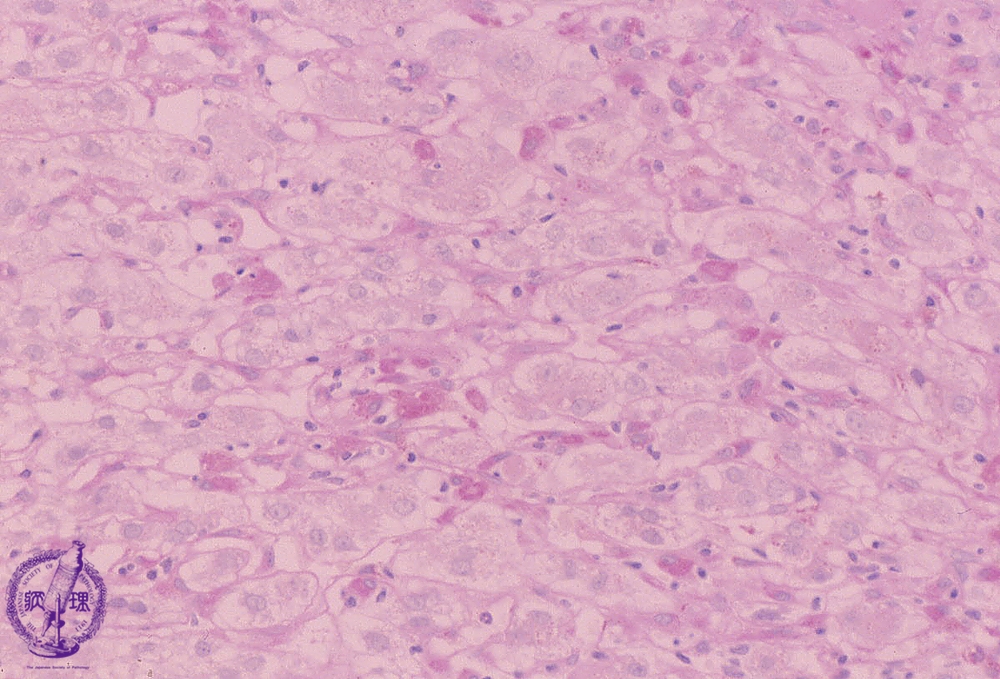

Microscopic image (PAS diastase stain, high power): Within sinusoids, numerous diastase resistant PAS positive histiocytes (Kupffer cells) are seen. These changes are observed in association with acute liver injury.